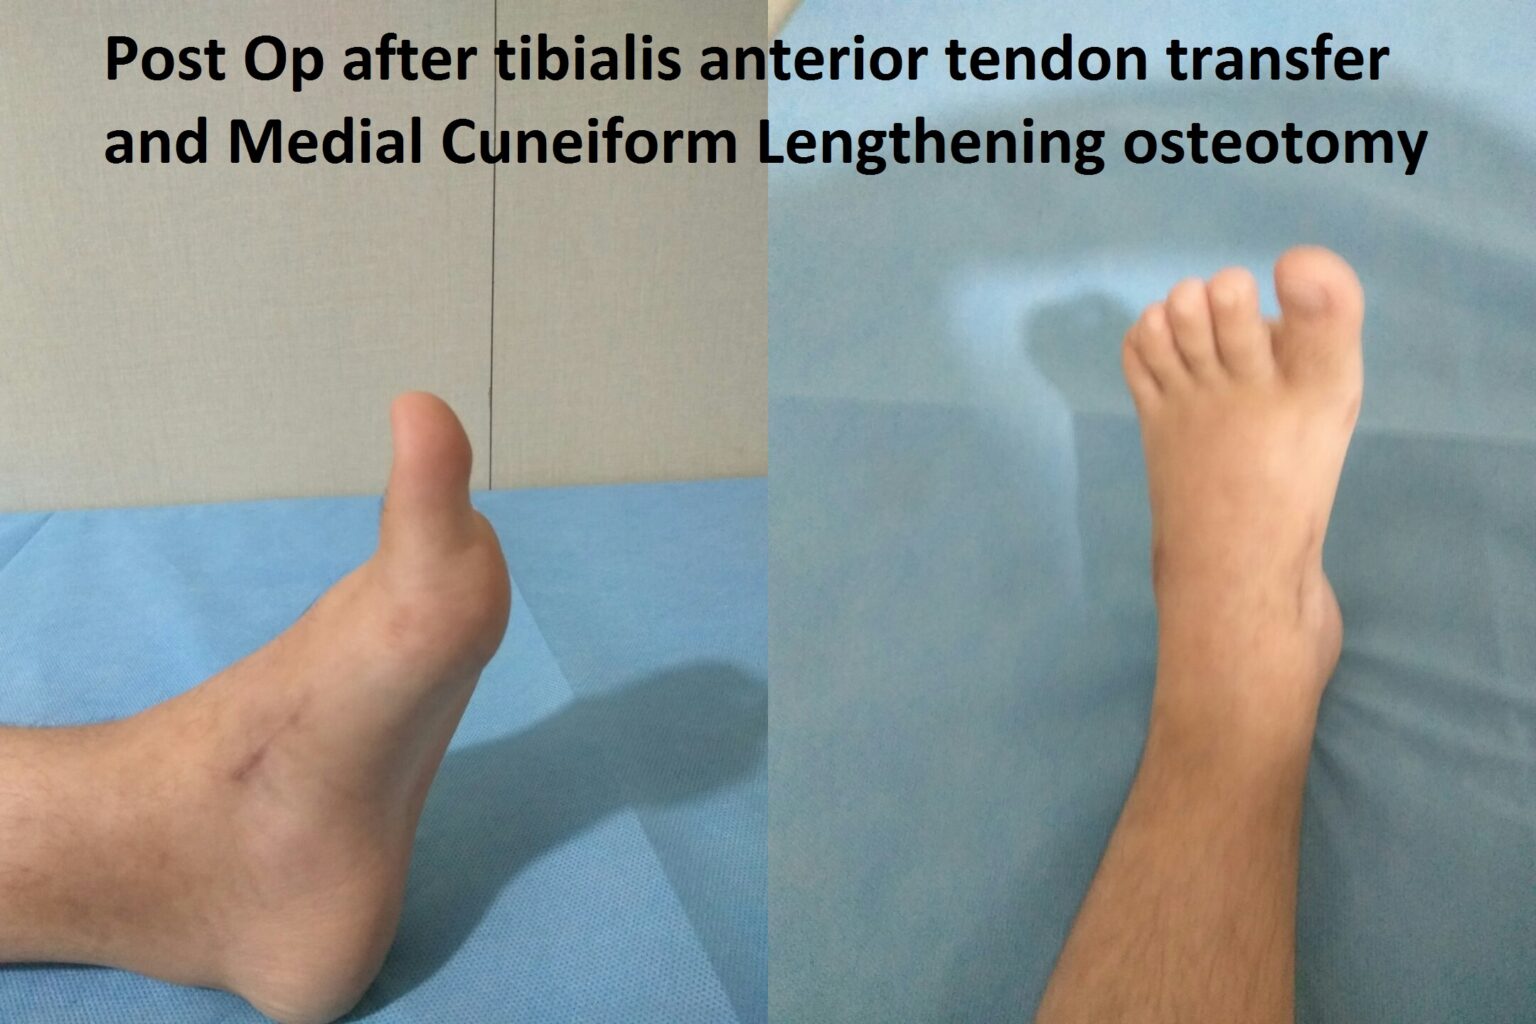

The recurrence is an unlikely phenomenon if a proper bracing protocol is followed. There could be minor relapse with dynamic supination and in-toeing when in 10-20% of patients, a Tibialis Anterior muscle transfer might be necessary.

Case Illustration

A 6-year-old girl presents with a recurrence of club foot. She developed dynamic supination and was treated with tendon transfer and medial column lengthening to get a good plantigrade foot.